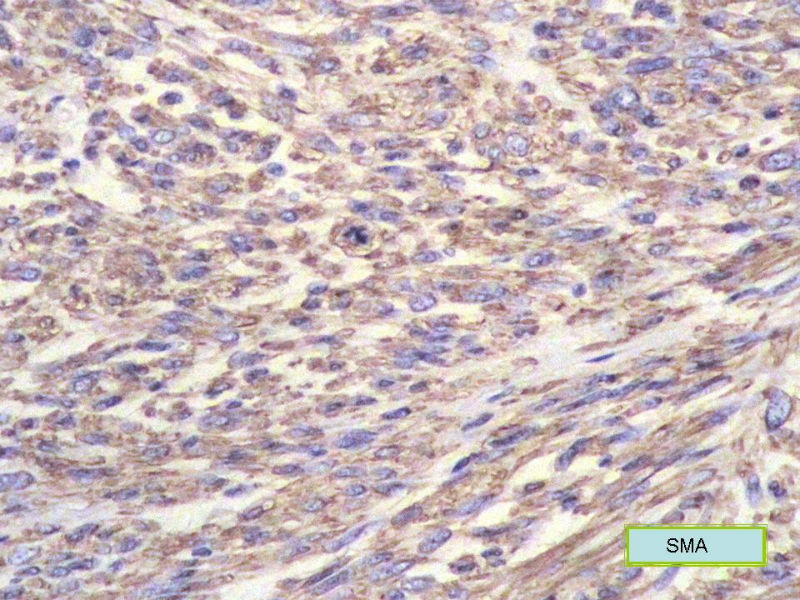

女,71岁,胸闷2月余,CT提示纵膈占位。手术见左肺与胸膜之间有一肿块,与周围粘连,手术切除。肉眼,肿块7X5X3厘米,边界较清楚,切面灰白灰红,质韧。

镜检:核分裂5</10HP

• 纵膈占位,新加免疫组化图1

图1

• 纵膈占位,新加免疫组化图2

图2

此例我们诊断为平滑肌肉瘤,因为很少见,请各位老师讨论!

形态学和免疫组化标记符合平滑肌肉瘤,但要标记Myogenin等鉴别横纹肌肉瘤,标记D2-40、Calretinin等鉴别肉瘤样间皮瘤。